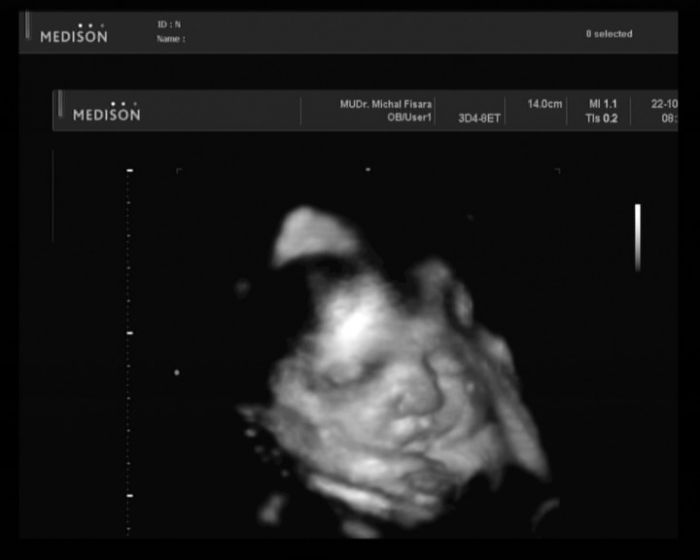

Ahoj holky.Tak jak si užíváte slunečnej víkend?Já jsem si myslela, jak půjdu na procházku a nakonec mam co dělat abych vůbec uklidila.Nic mi neni, nemám chřipku ani mě nebolí břicho, ale jsem strašně unavená.Už od včera.Taky to občas máte?Doufám, že už mě to přejde.Možná že na mě něco leze, jen se to ještě neprojevuje.Nevim no.Jinak zítra jdu konečně na cukr, tak jsem zvědavá a ve středu na 4D ultrazvuk.Už se moc těšíme.Taky by mi měl přijít tenhle týden mantinel a povlečení do postýlky.Aspoň se mi zlepší nálada :) Furt nějak řešíme peníze, rekonstruujem barák a stále je to kam strkat.Ještě stále nemam kočárek, ikdyž mam na něj peníze.Nevim na co čekám.No už si ho musim konečně koupit a radovat se co to dá.Tak snad jste veselejší a energičtější než já.Krásnej den přeju

Co 4D ultrazvuk ? Jak se ti líbil ? Nic si z toho nedělej, peníze taky řešíme. A to máme své bydlení, ale manžel podniká, tak jich není holt nazbyt. Ale věřím, že bude lépe.